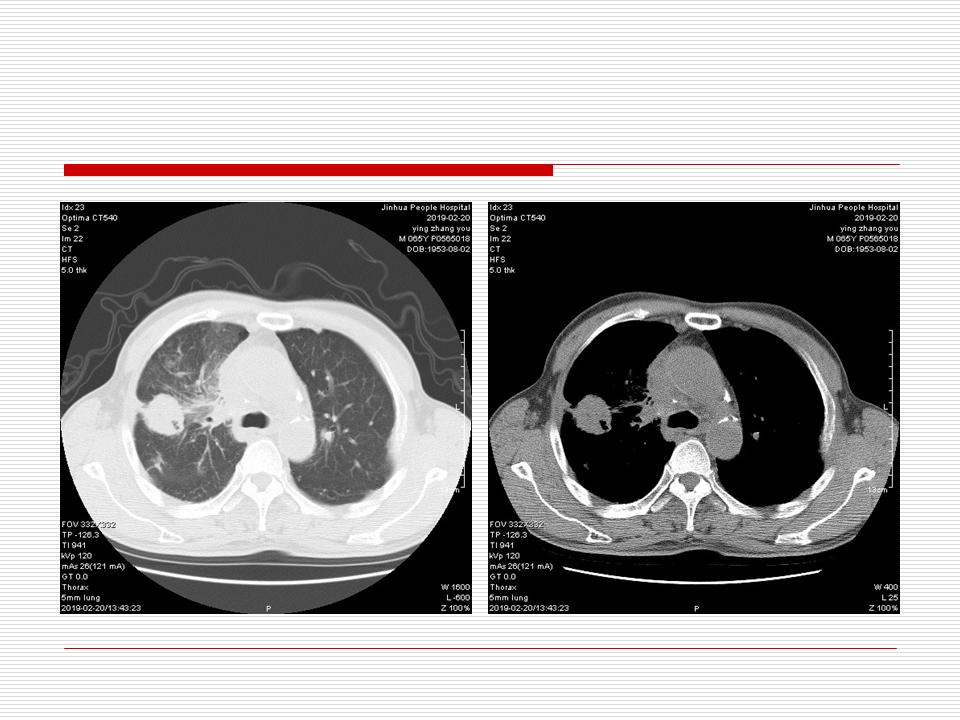

肺部阴影永恒且最重需要鉴别的是:到底是炎症还是肿瘤?但临床的病例中的影像表现难以界定或有些肿瘤特征,同时又有些炎症特点是非常常见的情况。作为临床医生我们怎么去总结分析,并找到之所以是炎症或之所以是肿瘤的细微差别或特点非常重要,也非常有用。2019.12.7浙江省2019年胸心外科学学术年会在宁波召开时,我的临床病例分析与经验总结<那些像肺癌的炎症与像炎症的肺癌>获得在大会交流的机会,以下为该PPT的内容,与你分享,希望对同道有益,有借鉴与启迪。若有探讨与进一不完善的建议,欢迎文末留言讨论: